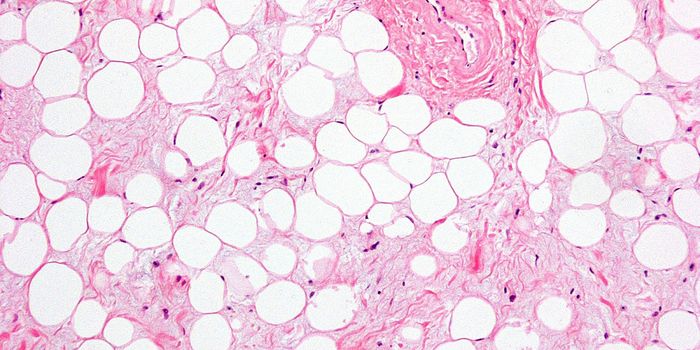

Cardiology is an ever-evolving branch of medicine concerned with disease and disorders of the heart. Cardiology trending provides articles and resources to keep you informed on risk factors, causes and prevention of heart disease, evidence-based research and advances in treatment.